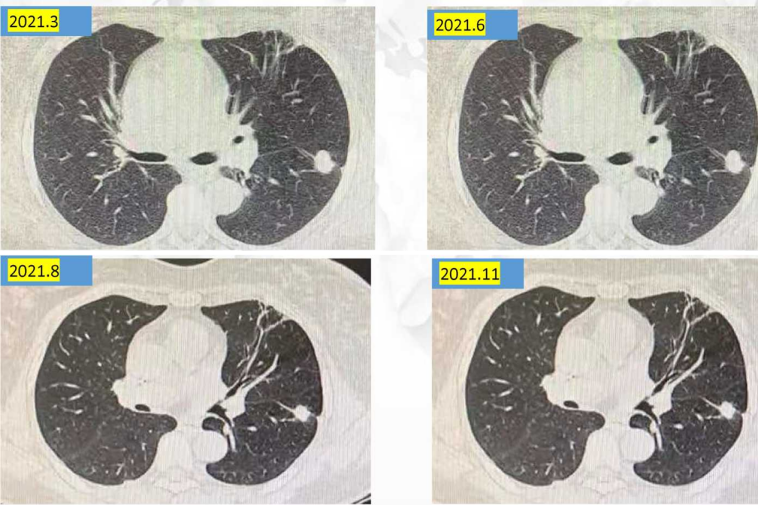

治疗方案:2021年1月-2021年7月,予长春瑞滨软胶囊40mg po tiw1,3,5节拍化疗+依维莫司5mg qd联合曲妥珠单抗+帕妥珠单抗治疗8个周期。

疗效评估:SD,PFS3为6个月。

疾病进展:2021年7月,颈、胸部CT显示,双肺多发结节较前略增大。